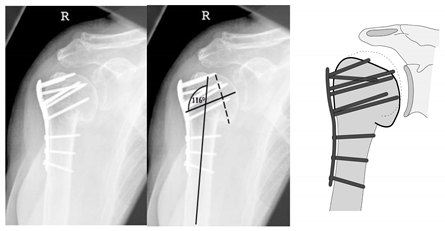

| Complication Type | Exemplary Images by X-rays or Pattern Images | Definition |

|---|---|---|

| 1 | ![]() | Complication Type 1 is defined by a mild, stable varus or valgus displacement (<20°) of the humeral head without resulting in a screw cutout through the humeral head cortex. |

| 2a | ![]() | Complication Type 2a is defined by varus displacement (<20°) of the humeral head associated with screw cutout through the humeral head cortex. The head sintering is considered relatively stable and non-progressive. |